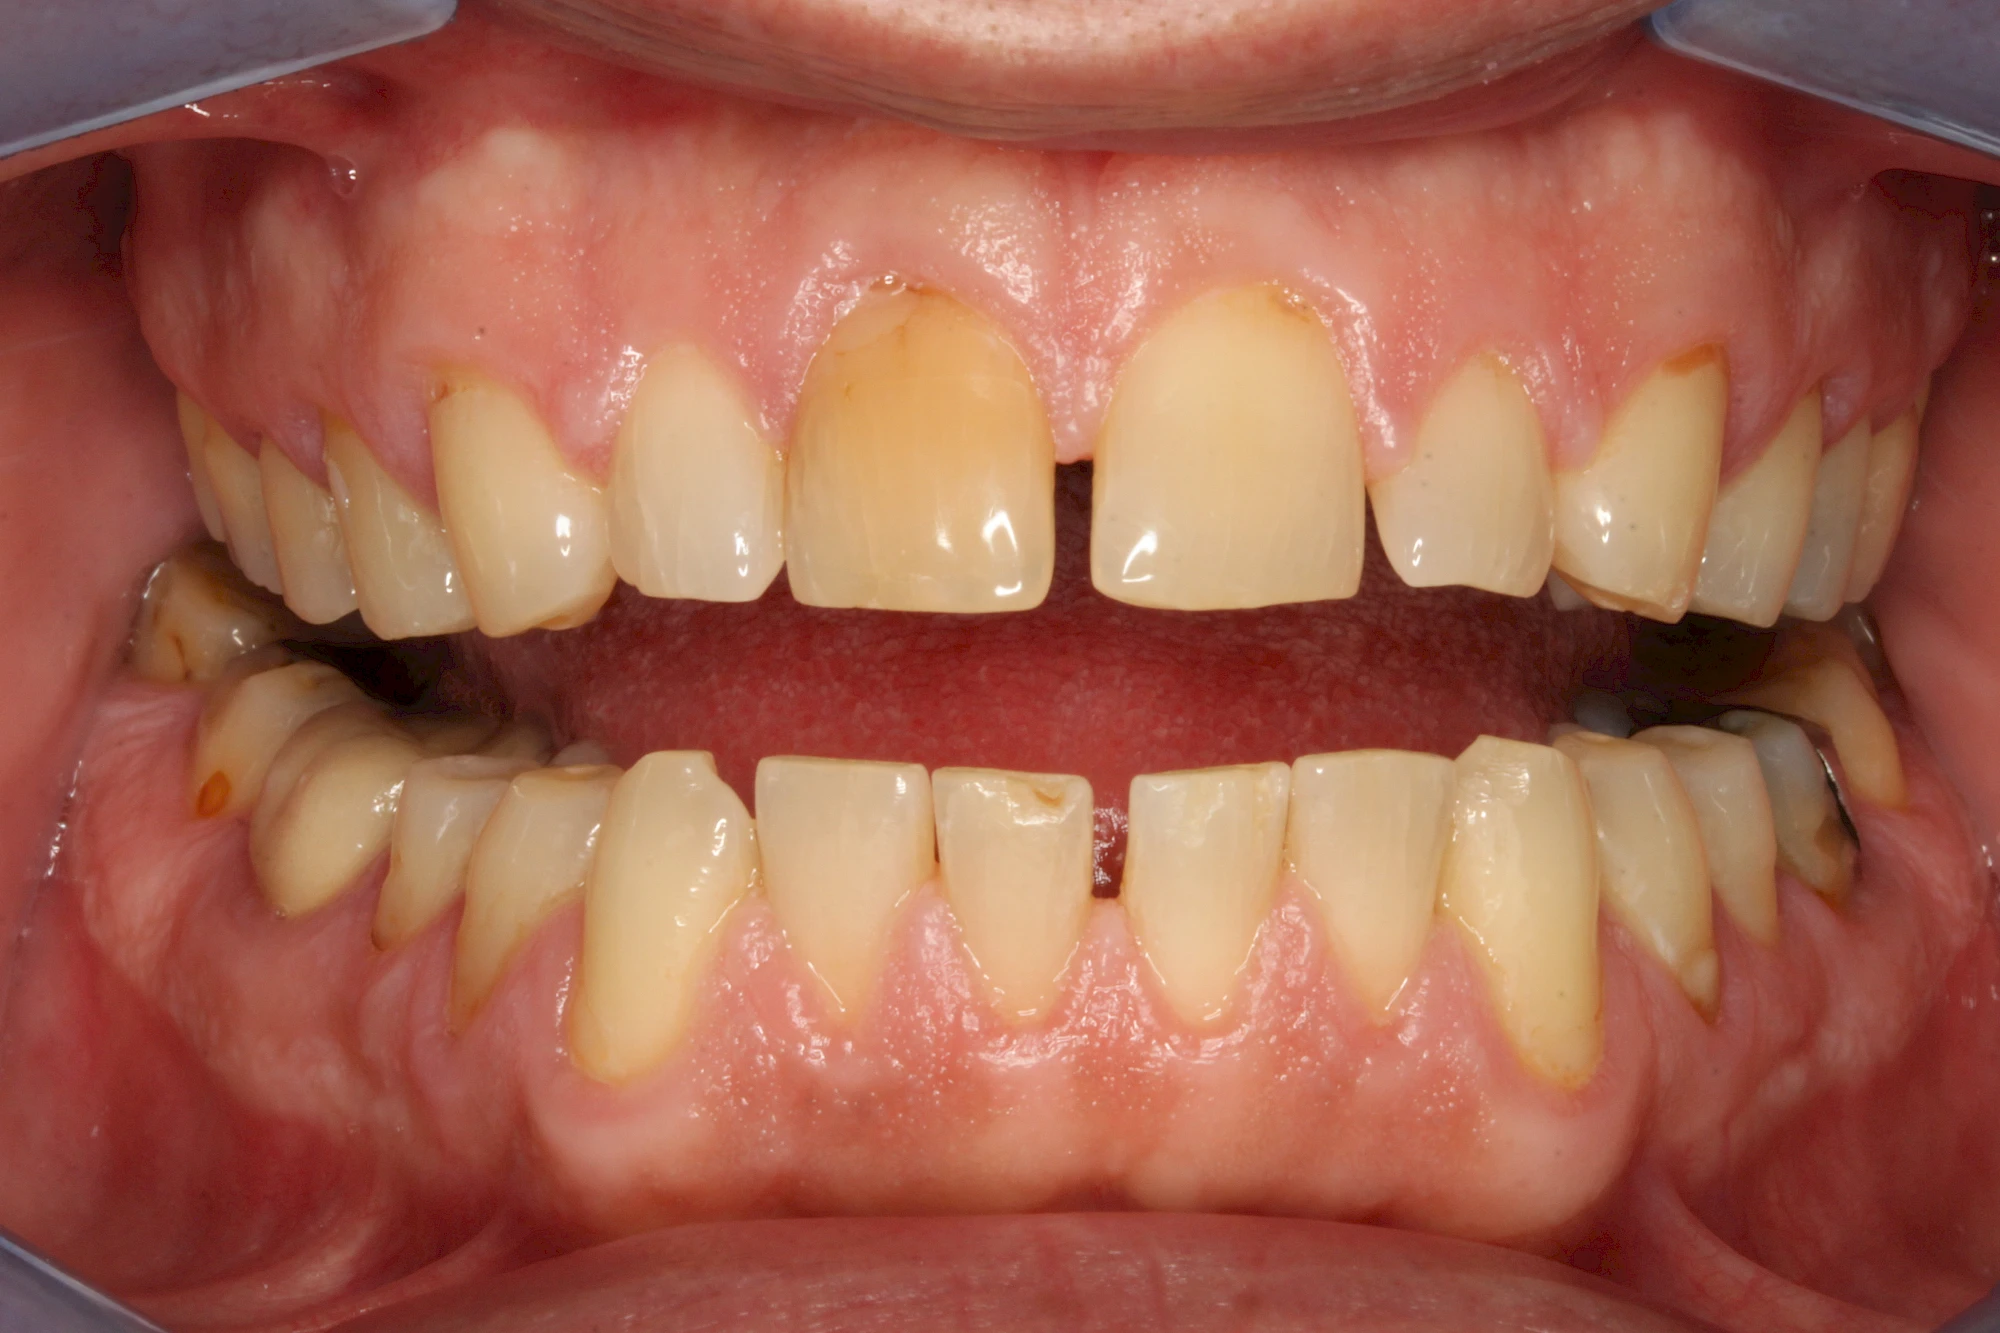

Verfärbungen an Zähnen können außen aufgelagert oder im Zahn eingelagert sein.

Von außen (exogen) eher dunkel gefärbt und meist mehrere Zähne betroffen:

- Genußmittel (Tee, Kaffee, Rauchen)

- Medikamente (z. B. Eisen)

Bräunliche Verfärbung

Äußere Verfärbungen durch Genußmittel oder Medikamente (Eisen!) lassen sich meist nur durch den Zahnarzt z. B. mit einer professionellen Zahnreinigung entfernen.